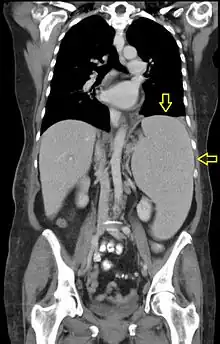

| CT scan in a patient with chronic lymphocytic leukemia, showing splenomegaly. Yellow arrows point at the spleen. | |

Splenomegaly is an enlargement of the spleen.[1] The spleen usually lies in the left upper quadrant (LUQ) of the human abdomen. Splenomegaly is one of the four cardinal signs of hypersplenism which include: some reduction in number of circulating blood cells affecting granulocytes, erythrocytes or platelets in any combination; a compensatory proliferative response in the bone marrow; and the potential for correction of these abnormalities by splenectomy. Splenomegaly is usually associated with increased workload (such as in hemolytic anemias), which suggests that it is a response to hyperfunction. It is therefore not surprising that splenomegaly is associated with any disease process that involves abnormal red blood cells being destroyed in the spleen. Other common causes include congestion due to portal hypertension and infiltration by leukemias and lymphomas. Thus, the finding of an enlarged spleen, along with caput medusae, is an important sign of portal hypertension.[2]

Abdominal CT is the most accurate. The spleen needs to be 2–3 times larger than normal to be palpable below the costal margin in physical examination.